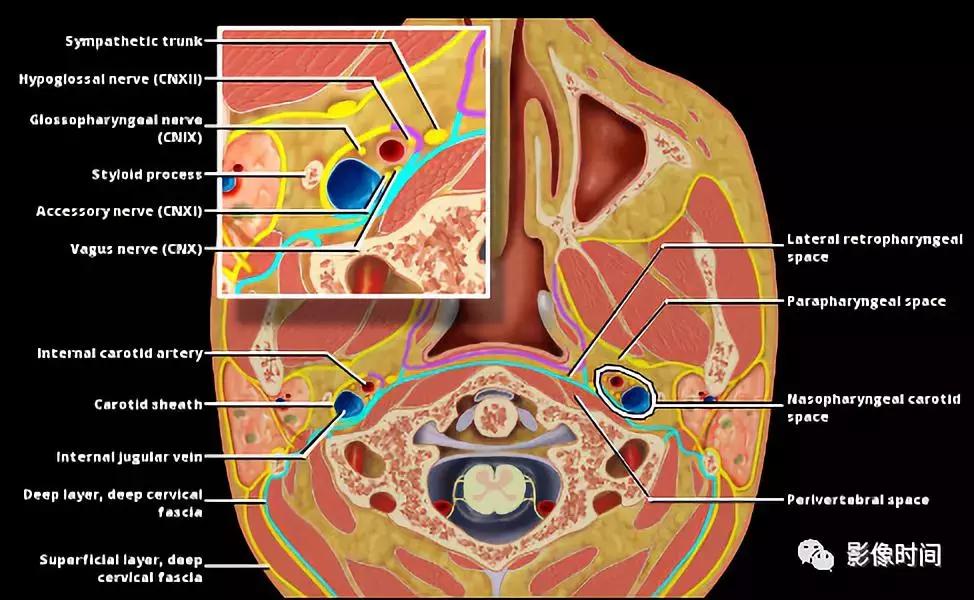

颈动脉间隙(carotid space,CS)是由颈动脉鞘包绕的颈部间隙,左右各一,由颈深筋膜的浅层、中层和深层构成。

颈动脉间隙上至颅底颈静脉孔,下至主动脉弓,由舌骨分为舌骨上区及舌骨下区。

舌骨上区-颈动脉间隙前方由咀嚼肌和咽旁间隙包围,外侧面被腮腺间隙包围,内侧面被咽后间隙包围,后面被椎前间隙包围。

结构包括:

1、颈内动脉

2、颈内静脉

3、9-12 对颅神经

4、交感神经丛

5、颈深淋巴结

舌骨下区-颈动脉间隙前方由颈前间隙包围,外侧面由胸锁乳突肌,内侧面由脏器和咽后间隙包围,后面由椎前和椎后间隙包围。

1、颈总动脉

3、第 10 对颅神经

颈内动脉是颈动脉间隙的中心,颈内静脉位于颈内动脉的后外侧。第 10 对颅神经(迷走神经)位于颈内动脉及颈内静脉之间的后方,而第 9/11/12 颅神经在舌骨上方水平穿出颈动脉鞘。